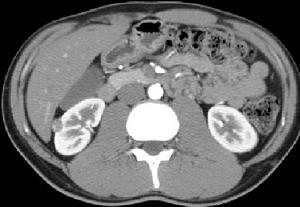

超聲檢查可見肝臟正常,腫瘤為圓形或橢圓形腫塊,小者僅2cm,邊界清晰,Doppler為少血 如果腫塊位於肝臟表面與腹壁有炎性粘連,常可在聲像圖上發現。CT掃描肝臟無硬化表現,脾臟不腫大,病變部門呈低密度影,邊界清晰,小的炎性假瘤很難與肝癌相鑑別。但注射造影劑後與血管瘤鑑別較易。MRI套用於肝臟診斷,肝臟炎性假瘤的肝臟表面光滑,門靜脈不擴張,脾臟不腫大,腫瘤在T1加權像上表現為低信號,病灶附近血管無受壓、變窄、移位, T2加權像上表現為高信號且邊界清晰。選擇性肝臟血管造影對於通過上述檢查不能診斷者具有重要意義,炎性假瘤表現為無血供或無血管增生像,這一點可與肝癌相鑑別。

綜合本組病例資料,以下幾點對診斷有幫助:(1)症狀輕,無明顯的陽性體徵,而且病程較長,本組最長1例為3.5年;(2)無肝臟病史,肝功能正常,HbsAg及AFP均陰性,本組有6例均正常;(3)BUS檢查多表現為邊界清楚的低回聲實質性腫塊,本組均有此種表現;(4)CT檢查多為邊界不清、密度不均勻的低密度區,本組均有此種表現。根據以上幾點仍不能確診應做肝臟穿刺檢查可作為定性診斷。有學者提出IPL的診斷要點主要包括:(1)多為肝右葉單發腫塊,短期內腫塊可縮小;(2)中老年男性多見;(3)常有發熱、肝區痛和消瘦乏力等表現;(4)外周血白細胞可升高,血沉和C反應蛋白可增加;(5)既往無肝病史,無肝硬化的表現;(6)腫瘤指標AFP和CEA正常;(7)腫塊B型超聲為低回聲,CT平掃為低密度,多無增強,延遲期呈現周邊增強;(8)血管造影為少血管影。